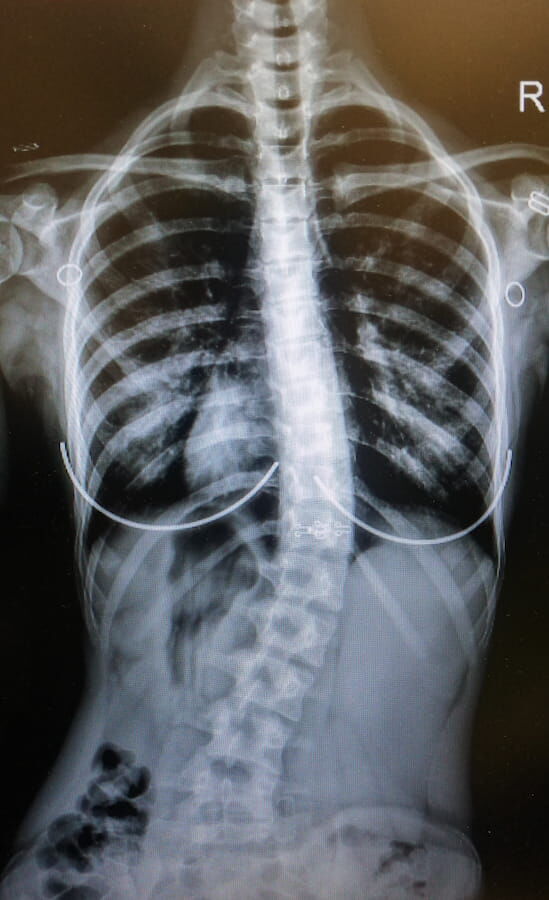

Результат коррекции при использовании корсета Шено и комплексов ЛФК по К.Шрот и ОКS